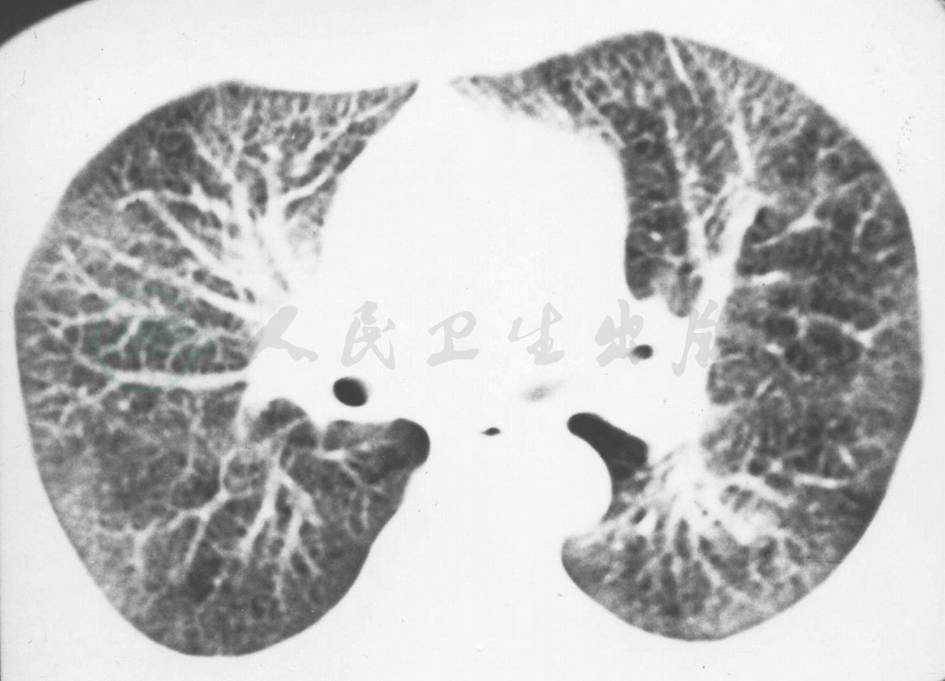

1.胸部HRCT

示双肺弥漫性小结节影,以周边分布为主,小叶间隔和叶间胸膜可见不规则结节状增厚,肺野内细小网状结节影 (图2)。

图2 胸部HRCT表现

HRCT较普通CT更加清晰地展示了患者肺间质病变的情况,表现为弥漫性肺结节影,结节与肺内淋巴引流相关,累及胸膜、小叶间隔、支气管血管束周围结缔组织,考虑为沿周边淋巴管分布的结节。